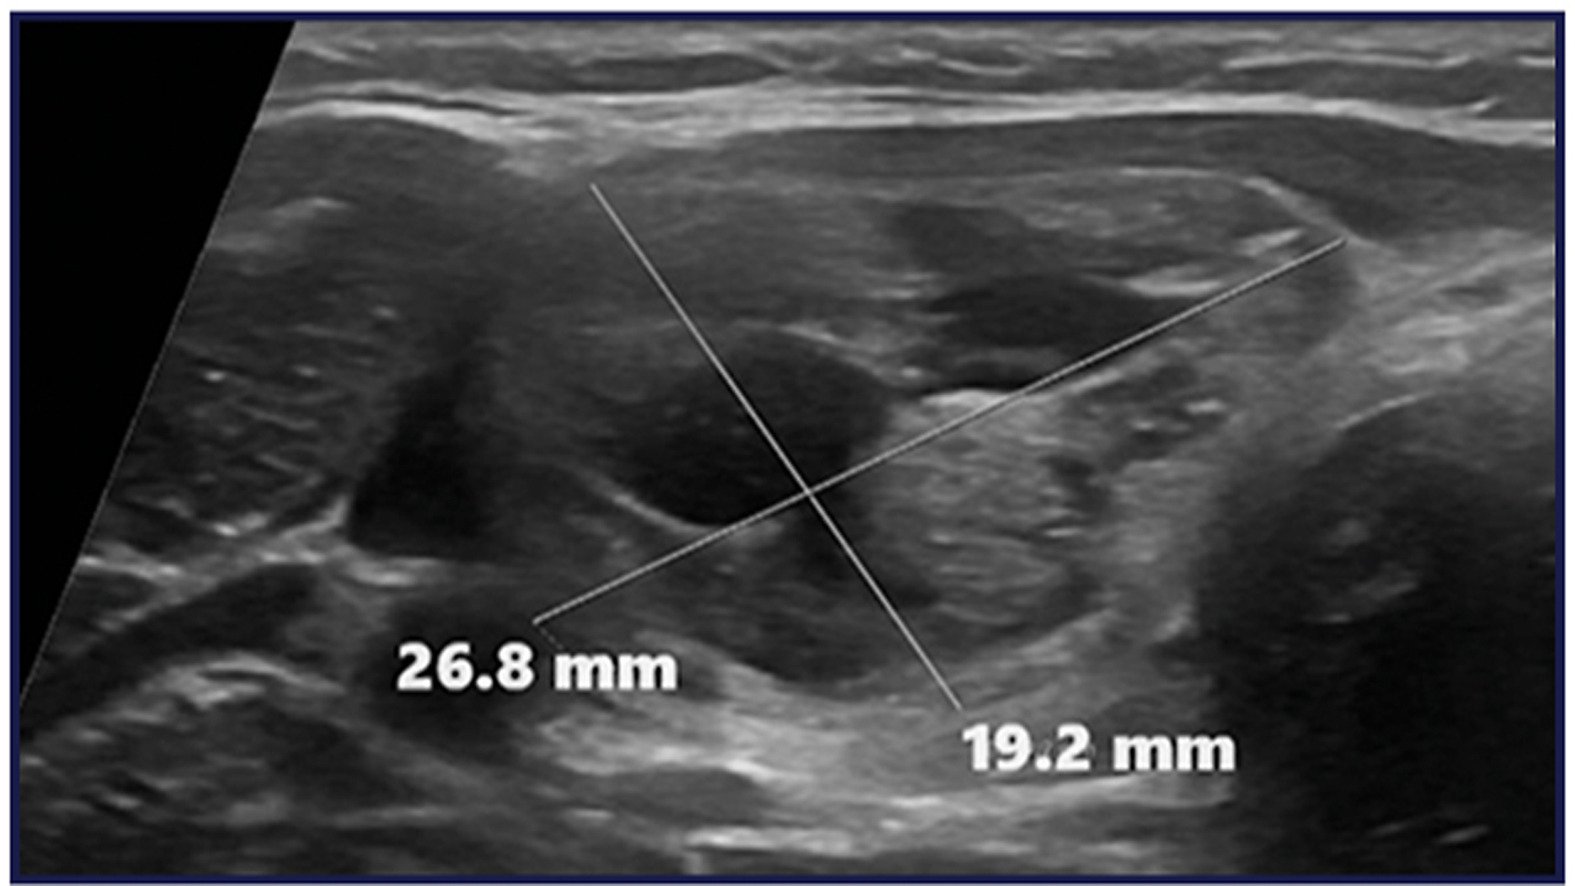

Dr. Szabo: Multinodular goiter is a common condition, particularly in iodine-deficient areas, and traditional treatments—such as surgery or radioiodine therapy—are not always feasible or preferred by patients. We were driven by the need for minimally invasive alternatives, especially for patients who are not surgical candidates or who decline surgery. While radiofrequency ablation (RFA) has shown excellent outcomes for isolated nodules, its role in treating large, complex multinodular goiters had not been well established. Our aim was to assess whether RFA could serve as a safe and effective alternative to total thyroidectomy in appropriately selected patients.

Dr. Szabo: RFA can achieve substantial and sustained volume reduction in large, symptomatic multinodular goiters—even in patients who would otherwise be surgical candidates.

Most patients experienced durable symptom relief and improved cosmetic outcomes, with a low complication rate. A staged treatment approach and selective retreatment of incompletely ablated or growing nodules can optimize long-term results. Thyroid function was preserved in all treated patients, including those with toxic nodules, who returned to a euthyroid state without surgery.